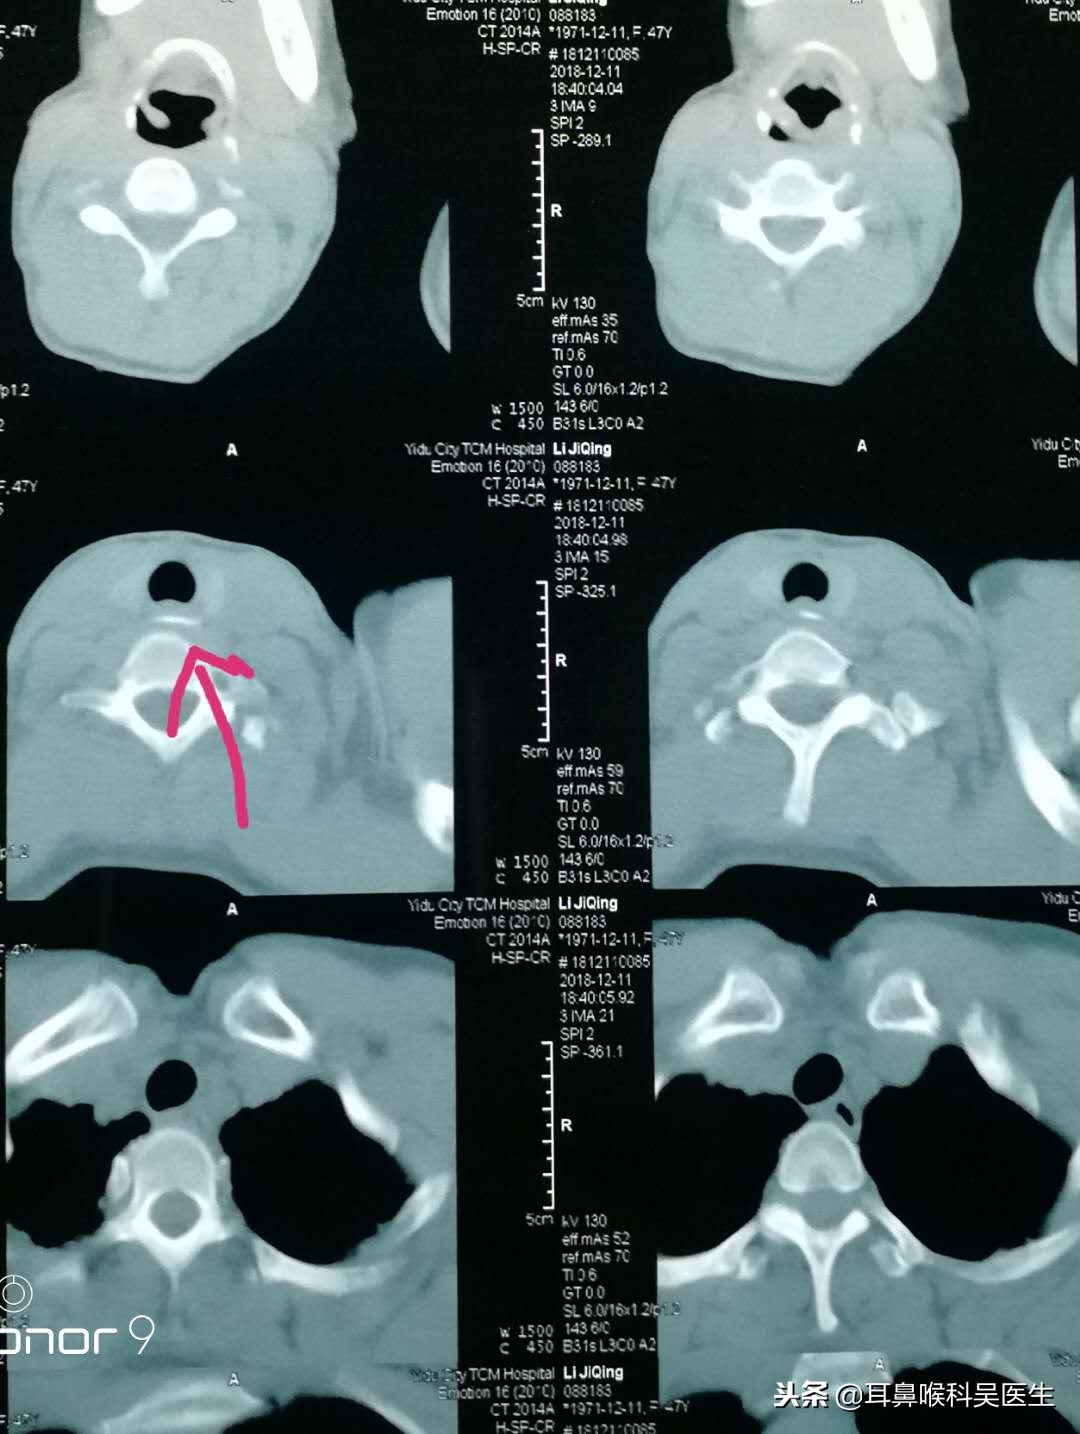

很多人误吞鱼刺等异物后时,不一定能弄清自己的异物到底卡在哪里,这时候,可以选择轻轻咳嗽一下,通过疼痛感来感知异物刺卡住的大概位子,从而判断是自行处理还是及时就医处理。误吞异物的常见被卡部位有左右扁桃体处、舌根部、会厌、食道、喉咙梨状窝。如果异物是在较浅的部位,可通过肉眼观察看到的,可以在现场尝试自行夹出。但如果是卡在比较深的部位如会厌、舌根等位子,则需要通过医院专业器材来取出。这些部位黏膜柔软脆弱,食道相邻还有大血管,错误处理鱼刺等异物,可能会让食道出血,黏膜受伤发炎等。

3.尽快到医院就诊,通过喉镜、纤维支气管镜或异物钳取出。